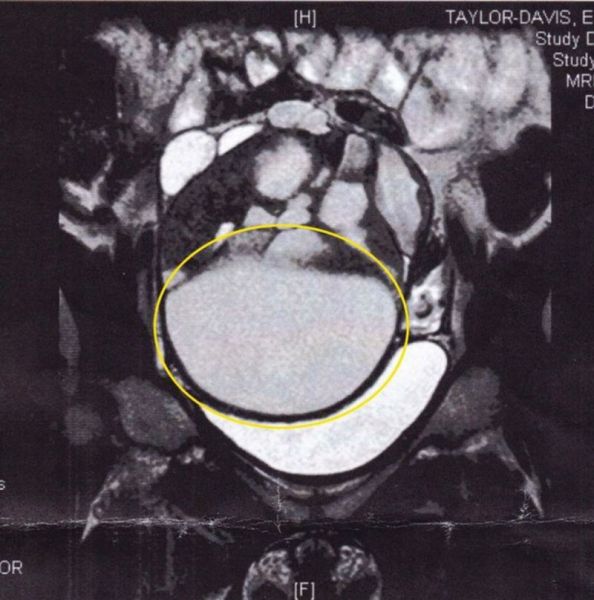

Και πώς όχι, όταν η Έλι Τέιλορ Ντέιβις οφείλει στην κυριολεξία τη ζωή της στο σεξ, αφού κατά τη διάρκεια μιας ερωτικής συνεύρεσης με το σύντροφό της ανακάλυψε έναν «εξωγήινο» όγκο 16 εκατοστών στις ωοθήκες της, ο οποίος συνέθλιβε τα όργανά της.

Η συγγραφέας από το Ίσλινγκτον του Λονδίνου, ανακάλυψε την ανατριχιαστική αλήθεια ένα μήνα αργότερα σε μία επίσκεψη ρουτίνας στο γυναικολόγο της. Το υπερηχογράφημα επιβεβαίωσε πως ένας όγκος 16 εκατοστών είχε αναπτυχθεί στις ωοθήκες και την κοιλιά της, απειλώντας τα όργανά της και την ίδια της τη ζωή!

Η έστω και καθυστερημένη διάγνωση αποδείχθηκε τελικά σωτήρια για την Τέιλορ -Ντέιβις, καθώς οι γιατροί κατάφεραν να αφαιρέσουν τον τεράστιο κακοήθη όγκο, χωρίς να χρειαστεί μάλιστα ακτινοθεραπείες. Πλέον βρίσκεται σε ύφεση, ενώ η ίδια θέλησε να μοιραστεί την ιστορία της προκειμένου να ευαισθητοποιήσει τον κόσμο στη μάχη κατά του καρκίνου, αλλά και να ενθαρρύνει τις γυναίκες να εξετάζονται τακτικά, όπως επίσης και να τις υποψιάσει για τα συμπτώματα που θα μπορούσαν να οδηγήσουν σε μια έγκαιρη και σωτήρια διάγνωση.